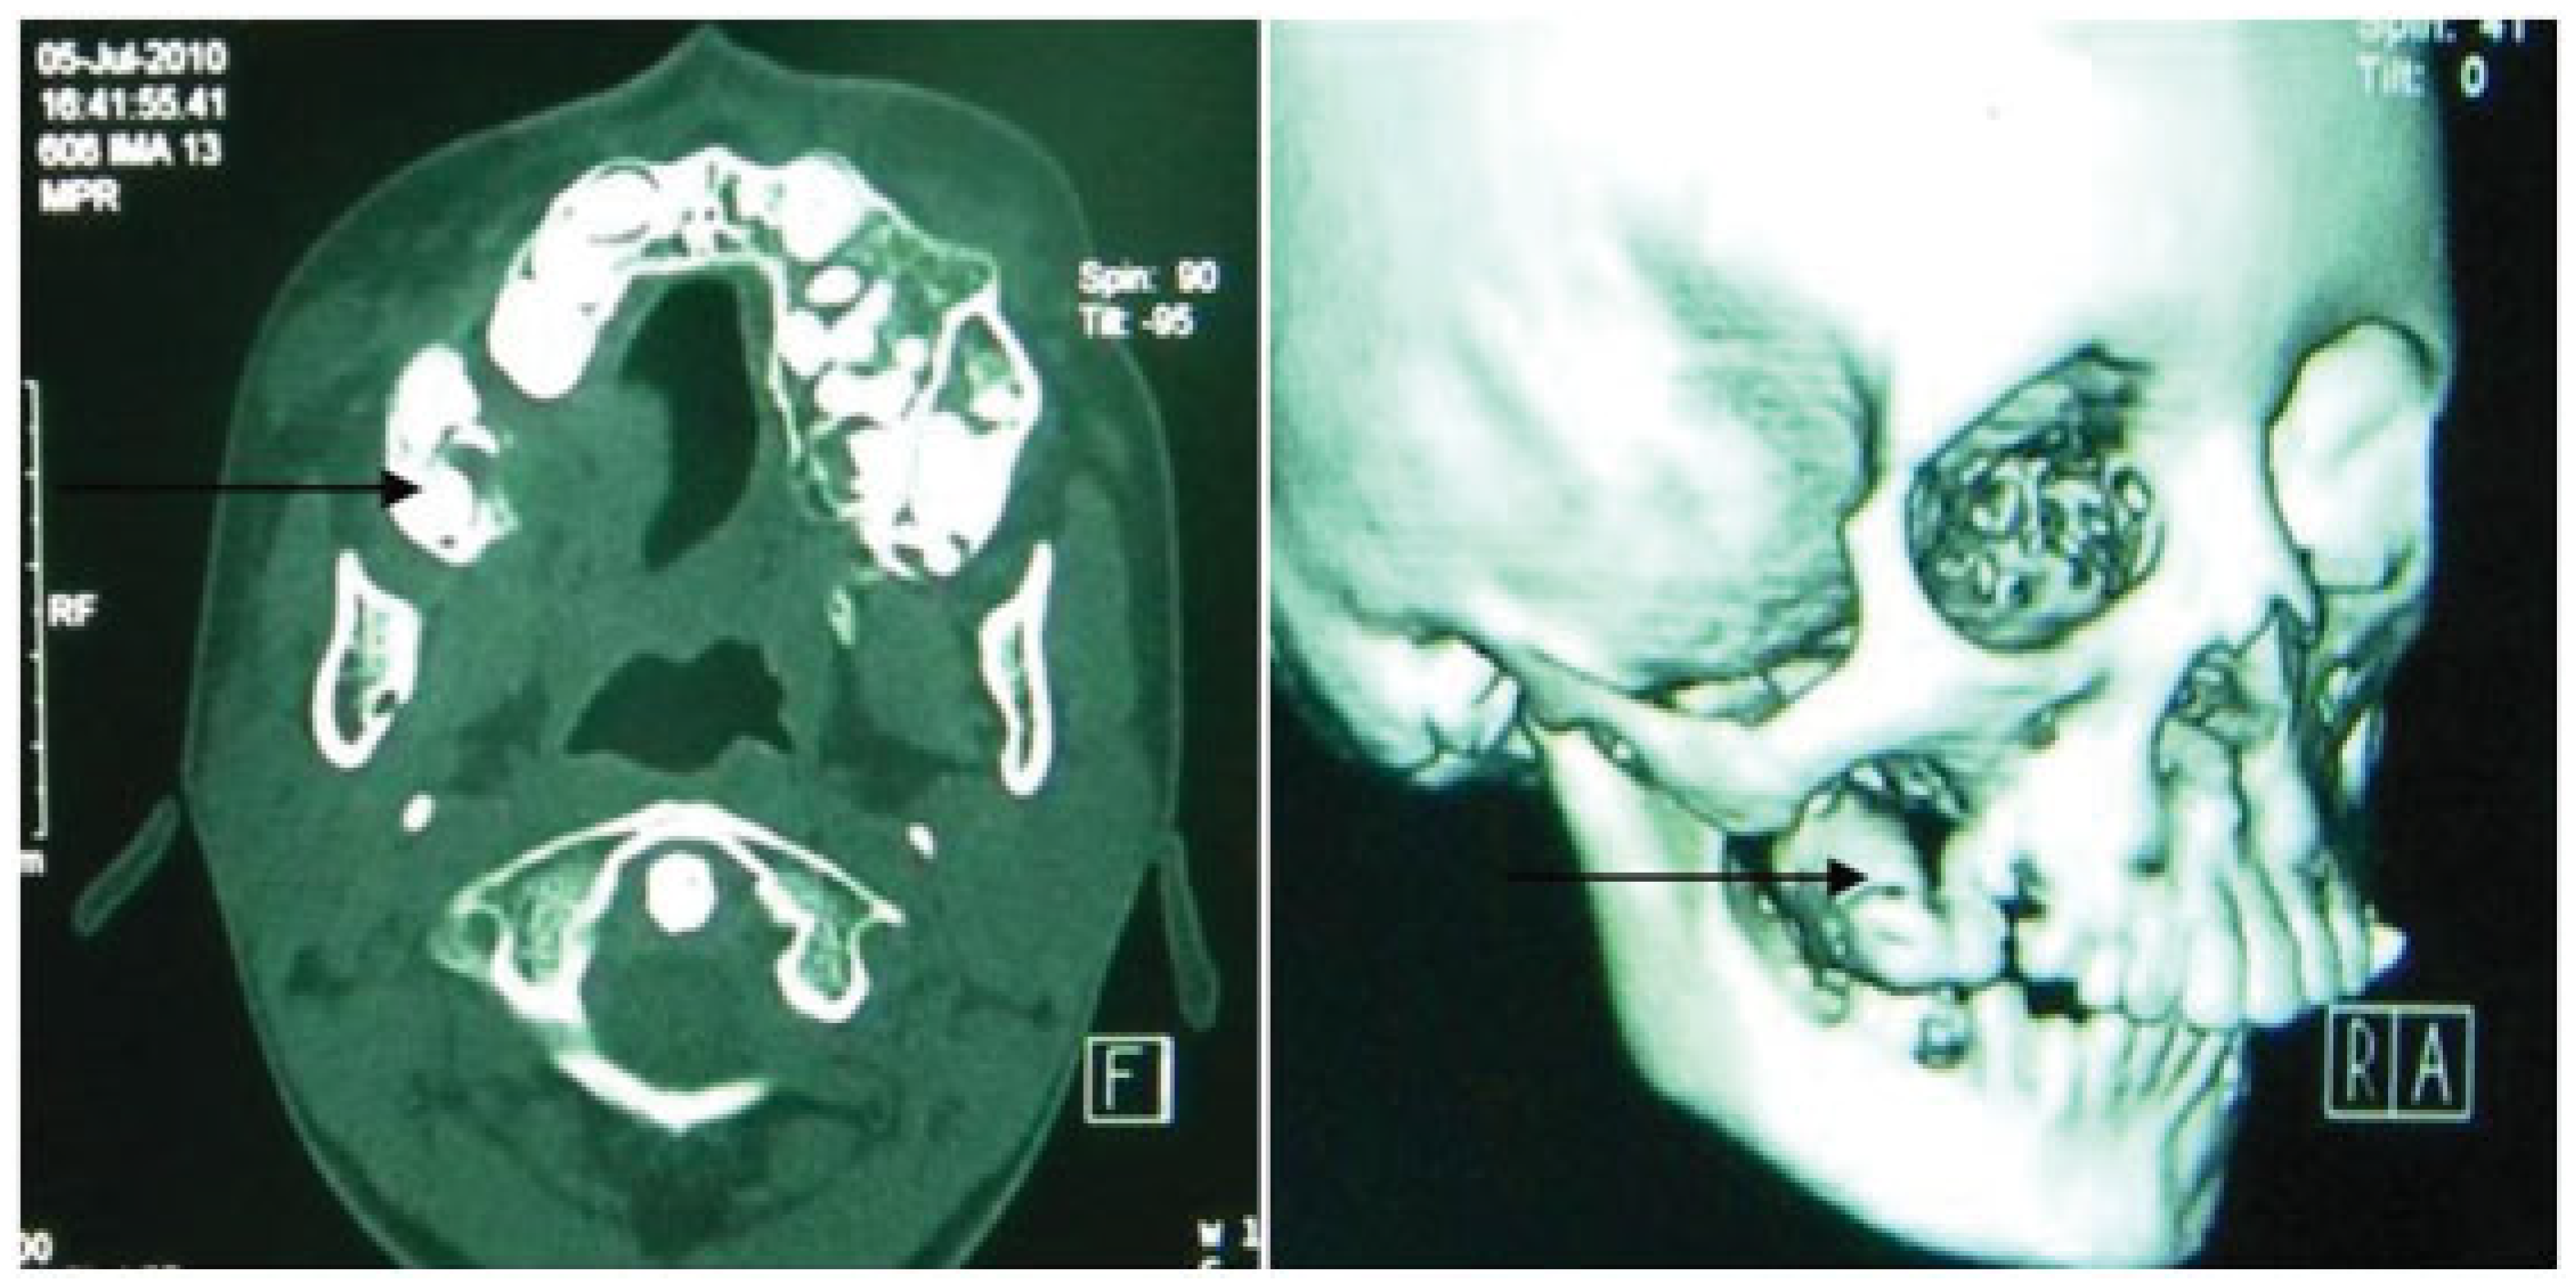

A Rare Case of Multiple Oblique Facial Clefts with Supernumerary Teeth: Case Report

- Incomplete Tessier 7 soft tissue facial cleft and a complete skeletal Tessier 7 cleft on the right side

- Incomplete Tessier 5 skeletal and soft tissue Tessier 6 facial cleft on the left side